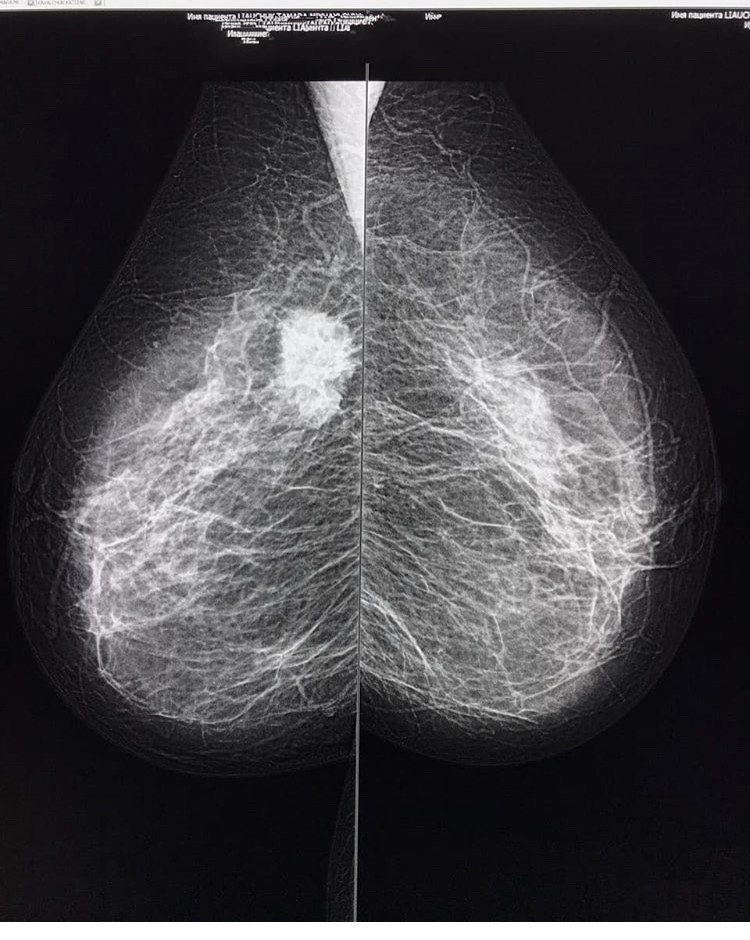

乳腺钼靶检查发现的乳腺癌,就是图片上那个白色的肿块,边界不清楚,有